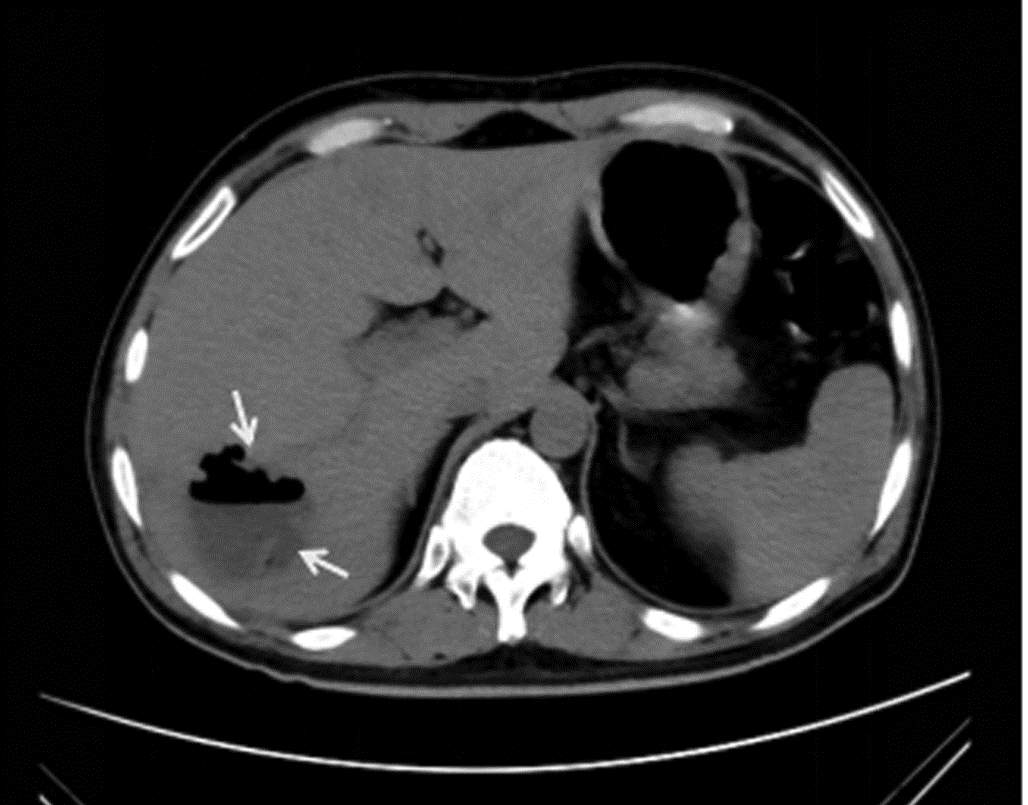

Hepatitis B cirrhosis with hepatic paragonimiasis misdiagnosed as primary liver cancer: A case report

Shenfeng HUANG, Jiajun LIN, Yang TAN, Zhifang CAI

2022, 38(6): 1367-1369. DOI: 10.3969/j.issn.1001-5256.2022.06.028

Abstract(985) HTML (273) PDF (2412KB)(52)

Abstract: